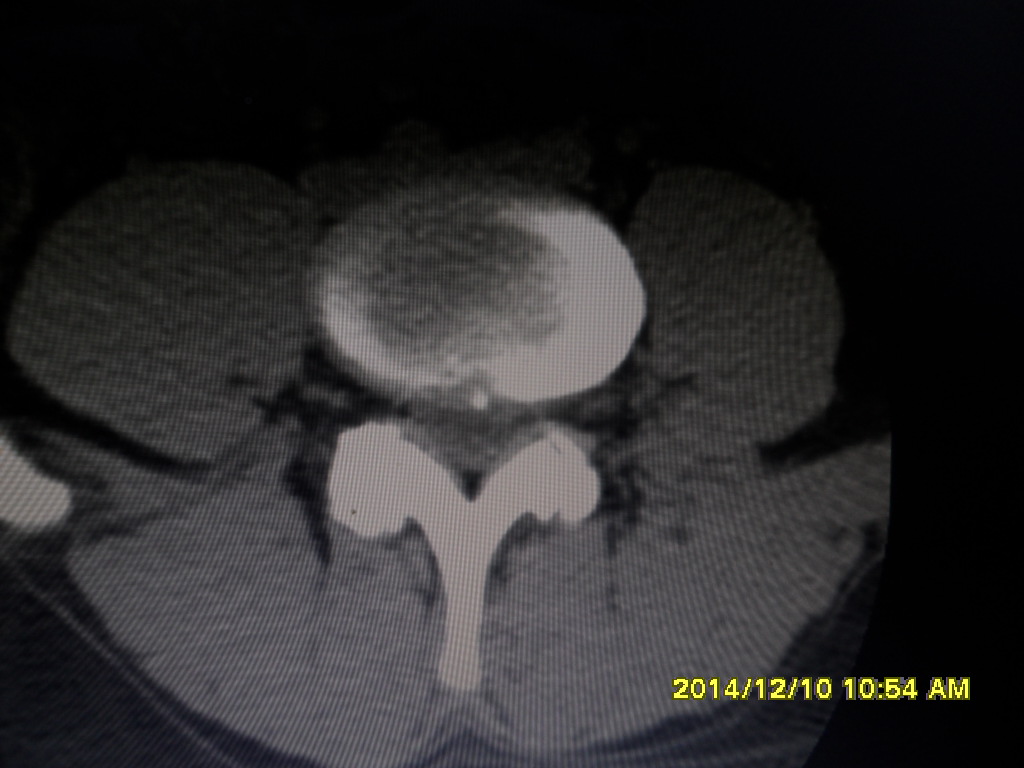

CT49557:椎间盘突出

L4-5椎间盘像左后突出 硬脊膜囊及左侧神经根受压

椎间盘突出